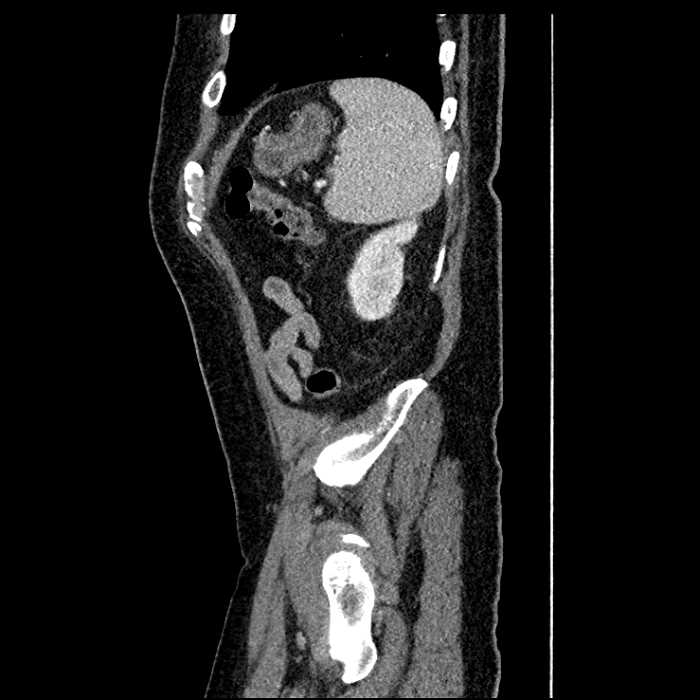

• Large fluid density structure in hepatic segments 7 and 8 measuring 10 x 7 x 7 cm with internal septation and circumferential ill-defined low density compatible with edema

• Peripherally enhancing subcapsular collections along the anterior margin of the left hepatic lobe measuring 3 x 1 cm and 2 x 1 cm

• Clearly marginated fluid density structure in segment 7 and several other scattered tiny hypodensities, which likely represent cysts

• Mild mural thickening of a segment of the sigmoid colon with adjacent fat stranding and a 1.5 cm fluid and gas collection along the tip of an inflamed diverticulum

• Loss of the normal fat plane between this collection and adjacent loops of small bowel, which demonstrate mural thickening

• Hepatic abscess

Acute sigmoid diverticulitis complicated by a small contained perforation and a large abscess in the right hepatic lobe. Additional small subcapsular abscesses along the anterior margin of the left hepatic lobe.

Additionally, loss of the normal fat plane between the peridiverticular collection and adjacent thickened loops of small bowel raises the potential for an enterocolonic fistula.

• The classic CT imaging appearance is a double target sign with internal low density surrounded by an internal enhancing rim (capsule) and a low density external rim (edema)

• Abscesses may be unilocular or multilocular

Hepatic abscess showing the double target sign with low density internally surrounded by a thin inner enhancing rim (red arrow) and ill-defined outer low density rim (yellow arrow). Blue arrow indicates an internal septation. Red arrows: additional smaller subcapsular abscesses. Red arrow: focal contained perforation associated with diverticulitis.